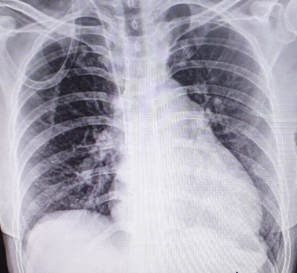

Φυσιολογική ακτινογραφία θώρακος δύο μήνες μετά την επέμβαση (Ευγενική παραχώρηση Dr. V. Penopoulos)